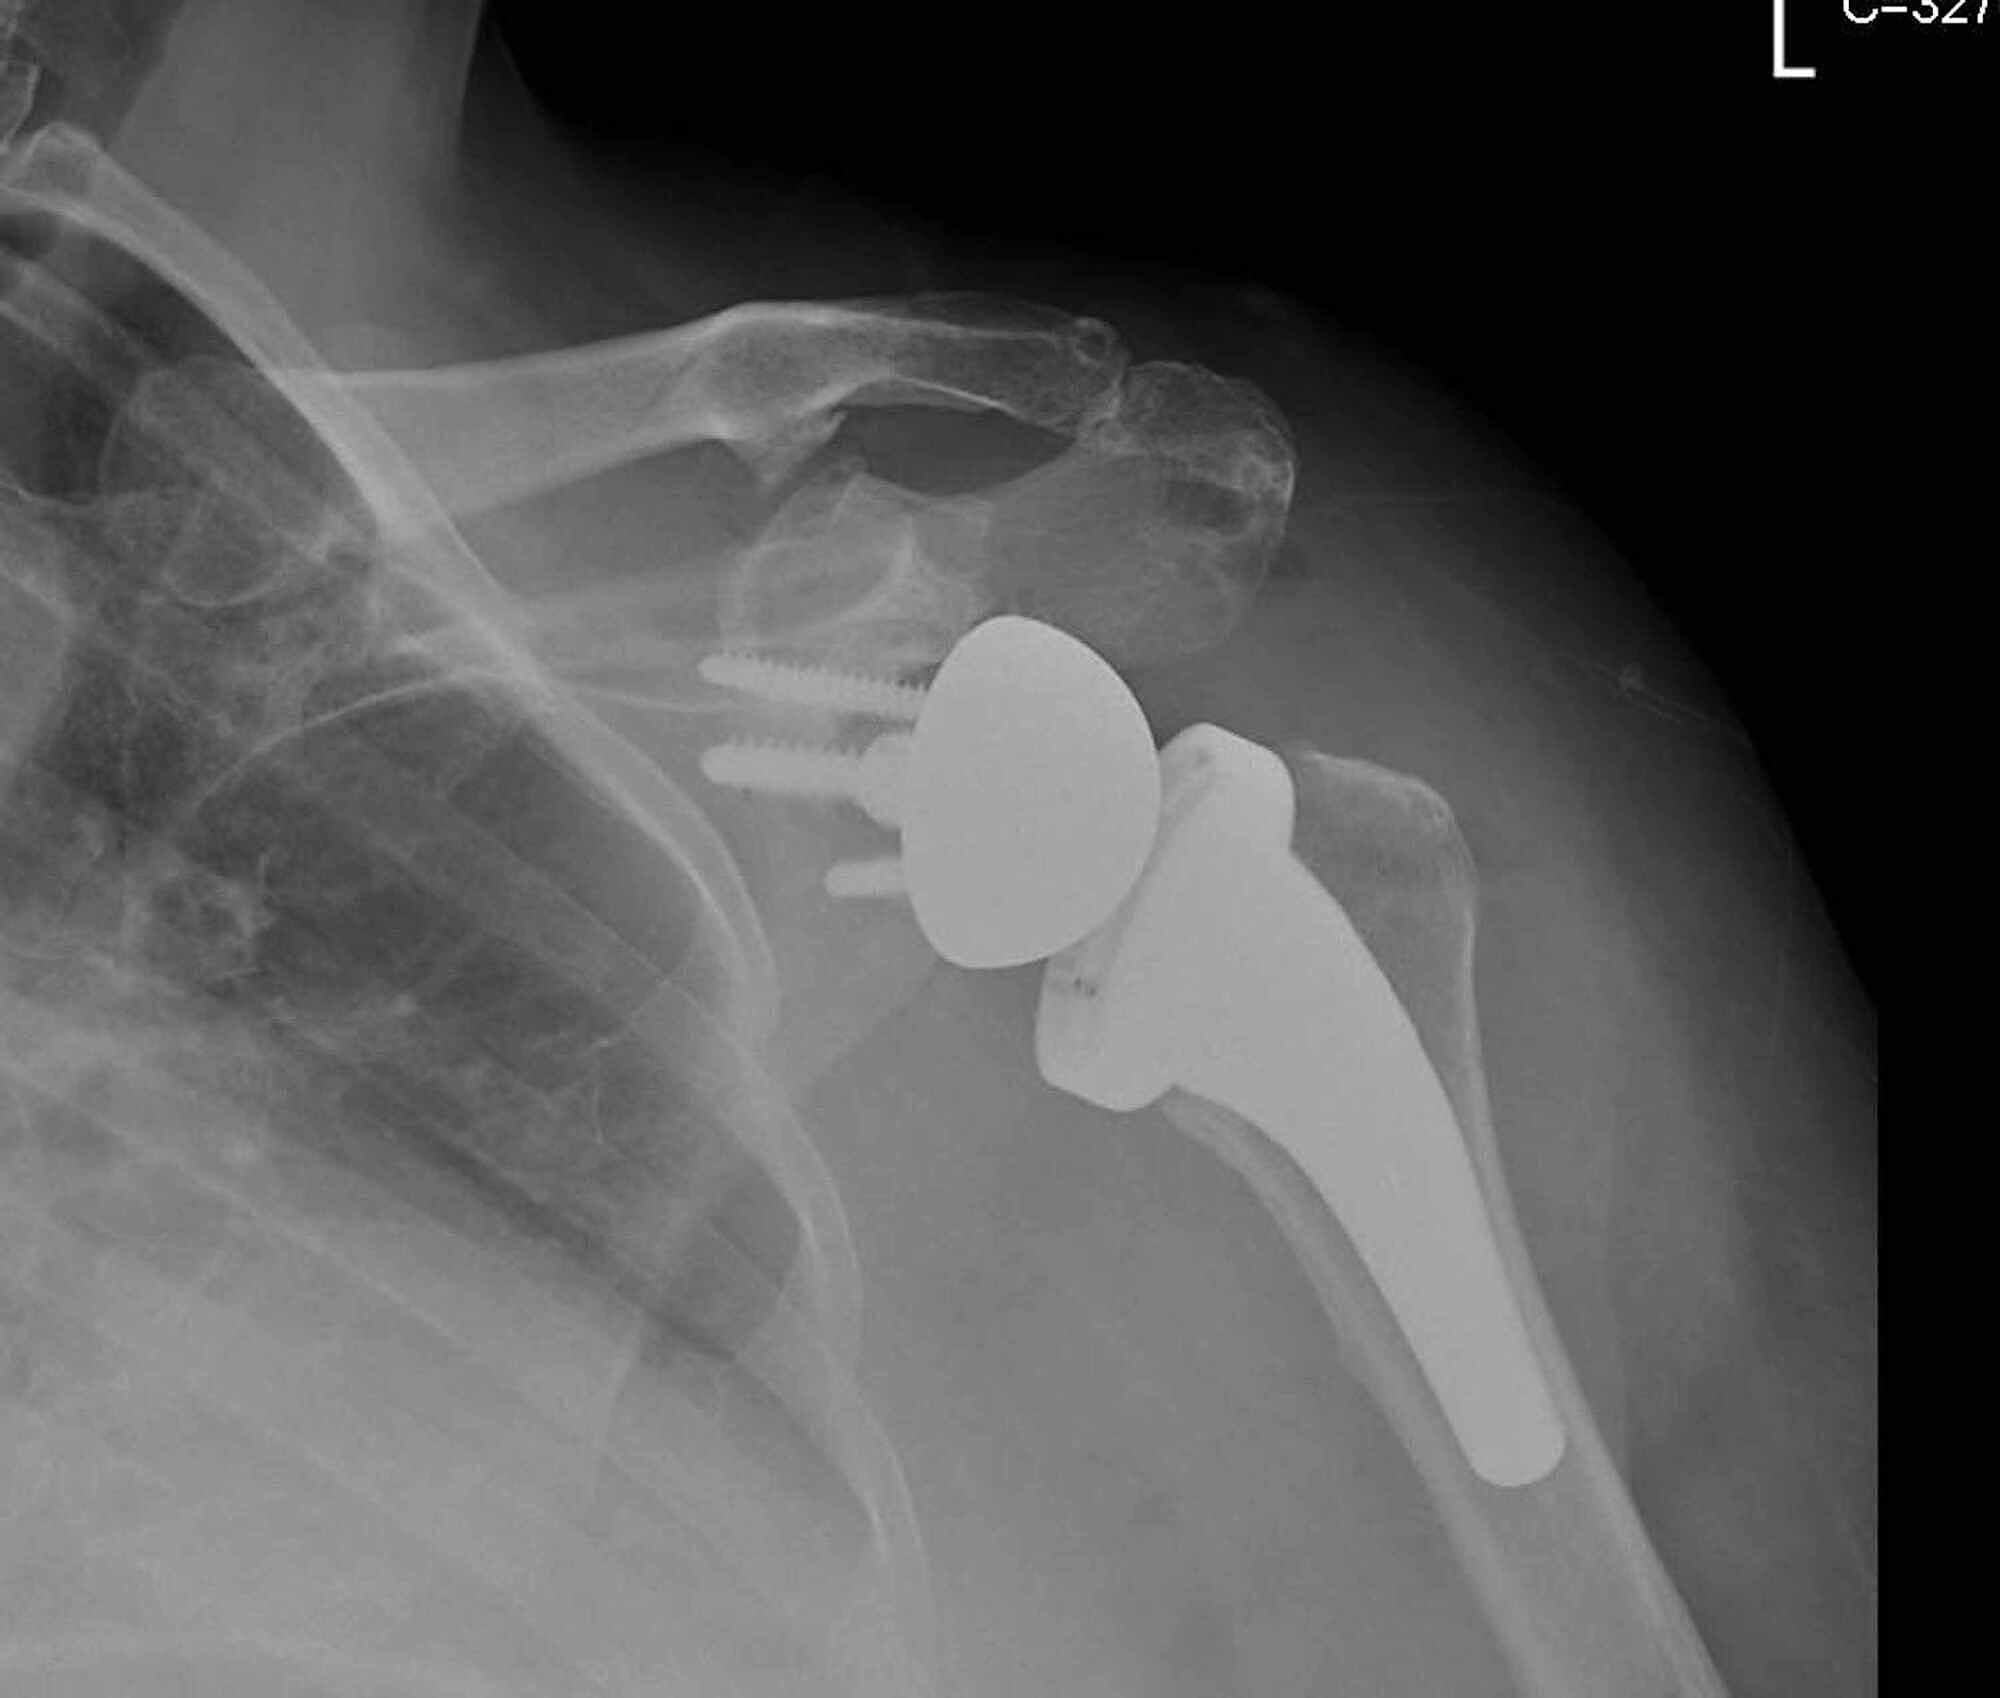

Cureus Scapular Spine Stress Fracture Following Reverse Total Scapula Fracture Physio Management Scapula fractures are uncommon fractures to the shoulder girdle caused by high energy trauma and associated with pulmonary. Most scapula fractures can be managed effectively with closed treatment. Return to activity or sport can usually take place. This information explains the ongoing management of your injury. The scapula (shoulder blade) is a bone, shaped somewhat like a triangle, that is. Scapula Fracture Physio Management.